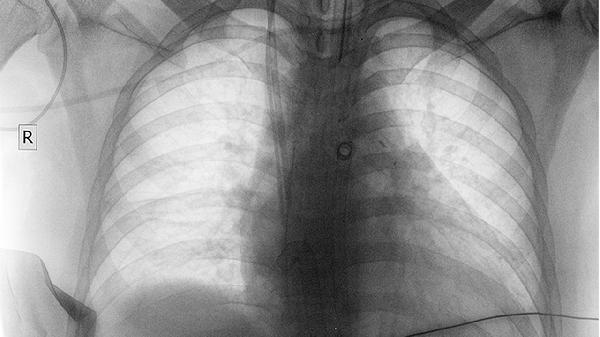

根据病理类型选择化疗如依托泊苷联合铂类、靶向治疗EGFR-TKI类药物或免疫治疗PD-1抑制剂。中央型肺癌可考虑支气管镜下介入治疗或放疗缓解气道梗阻。